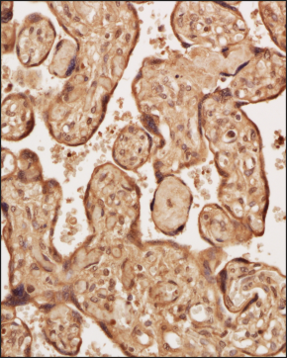

Somatostatin R5/SSTR5 Antibody - BSA Free Immunohistochemistry staining of Human Placenta

Immunohistochemistry staining of Human Placenta

Analysis of a FFPE tissue section of human placenta using 1:200 dilution of Somatostatin R5/SSTR5 antibody (NB100-56498). The staining was developed using HRP labeled anti-rabbit secondary antibody and DAB reagent, and nuclei of cells were counter-stained with hematoxylin.